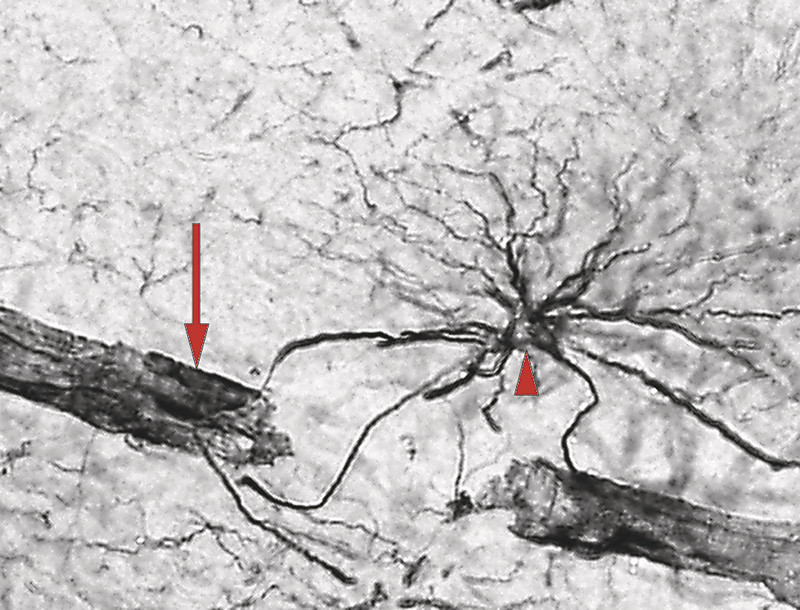

Figure 2  Astrocyte extending processes towards the brain parenchyma and blood vessels. Immunohistochemical visualisation of…

Figure 2 Astrocyte extending processes towards the brain parenchyma and blood vessels. Immunohistochemical visualisation of the potassium channel Kir4.1 in the human hippocampus. Astrocyte with processes (arrow head) and end-feet covering the surface of a blood vessel (arrow)